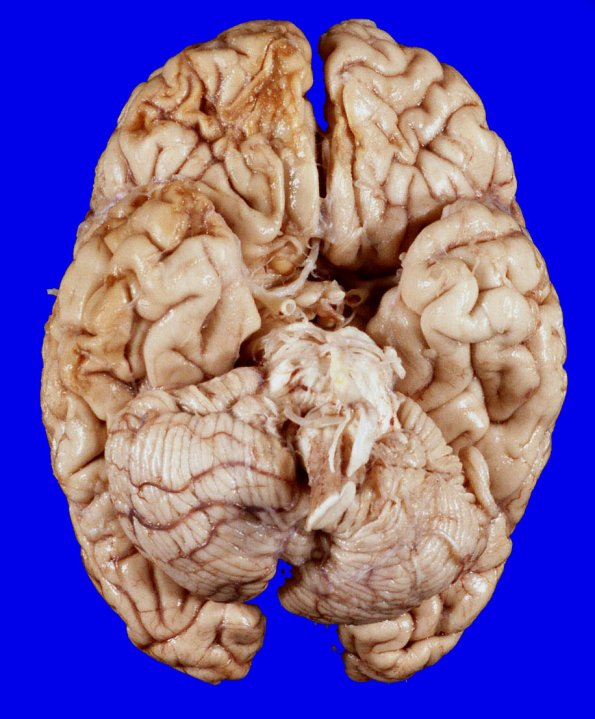

Case 20 History ---- The patient was a 63yo male with a history of stage III B cell lymphoma s/p chemotherapy, splenic rupture s/p embolization, paroxysmal atrial fibrillation, peptic ulcer disease, schizophrenia and depression who presented in the emergency department of BJH with abdominal pain, ascites and shortness of breath on 11/04. His EKG showed atrial fibrillation with no significant ischemic findings and a CT scan showed intra-abdominal and intrapelvic ascites, bilateral pleural effusions with left lower lobe consolidation, and an enlarged right heart with moderate tricuspid regurgitation. After few hours, his blood pressure dropped down below 90’s. The patient was started with IV fluids and antibiotics. However, his condition further worsened with abnormal electrolytes, hyponatremia, lactic acidosis and elevated liver enzymes. Despite supportive treatment, the patient eventually became unresponsive and was found to be breathless, pulseless and was pronounced dead on 11/05. The general postmortem exam failed to establish a cause of death. ---- At autopsy the weight of the unfixed brain was 1230g.

20A1,2 There are two brown-tan remote contusions (measuring 5 x 3 cm and 4 x 1 cm) on the right inferior frontal lobe and anterior aspect of the temporal lobe. It is possible that alcoholism indirectly resulted in the patient’s traumatic lesions, a common occurrence in such patients.